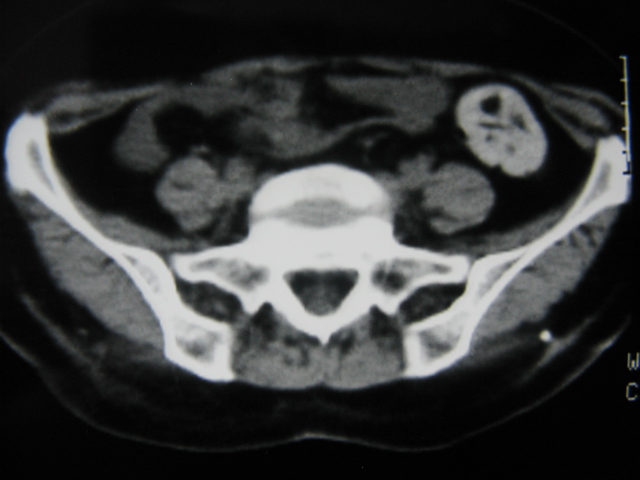

患者,女,64岁,2002年诊断为宫颈癌,当时只做过放,化疗。现在诊断:(1)宫颈癌。(2)直肠癌。请同道们讨论,探讨。另外肠壁为啥密度这么高,ct值约112hu。患者没有做过增强和造影。

高密度的不是肠管影,是肠管内的粪便影

患者直肠病变,排便不畅,粪便硬结造成,更高密度如钡灌肠者都可出现

硬结粪便能有如此高密度影?

我也碰到过几例,最离奇的一例是全结肠呈造影样高密度,患者直肠癌(首次发现),以往没有吃药,只有约半年时间长的胃纳差,排便不畅(据患者说每次大便只能拉出少许黄水)

不一定有意义,可清洁灌肠后复查